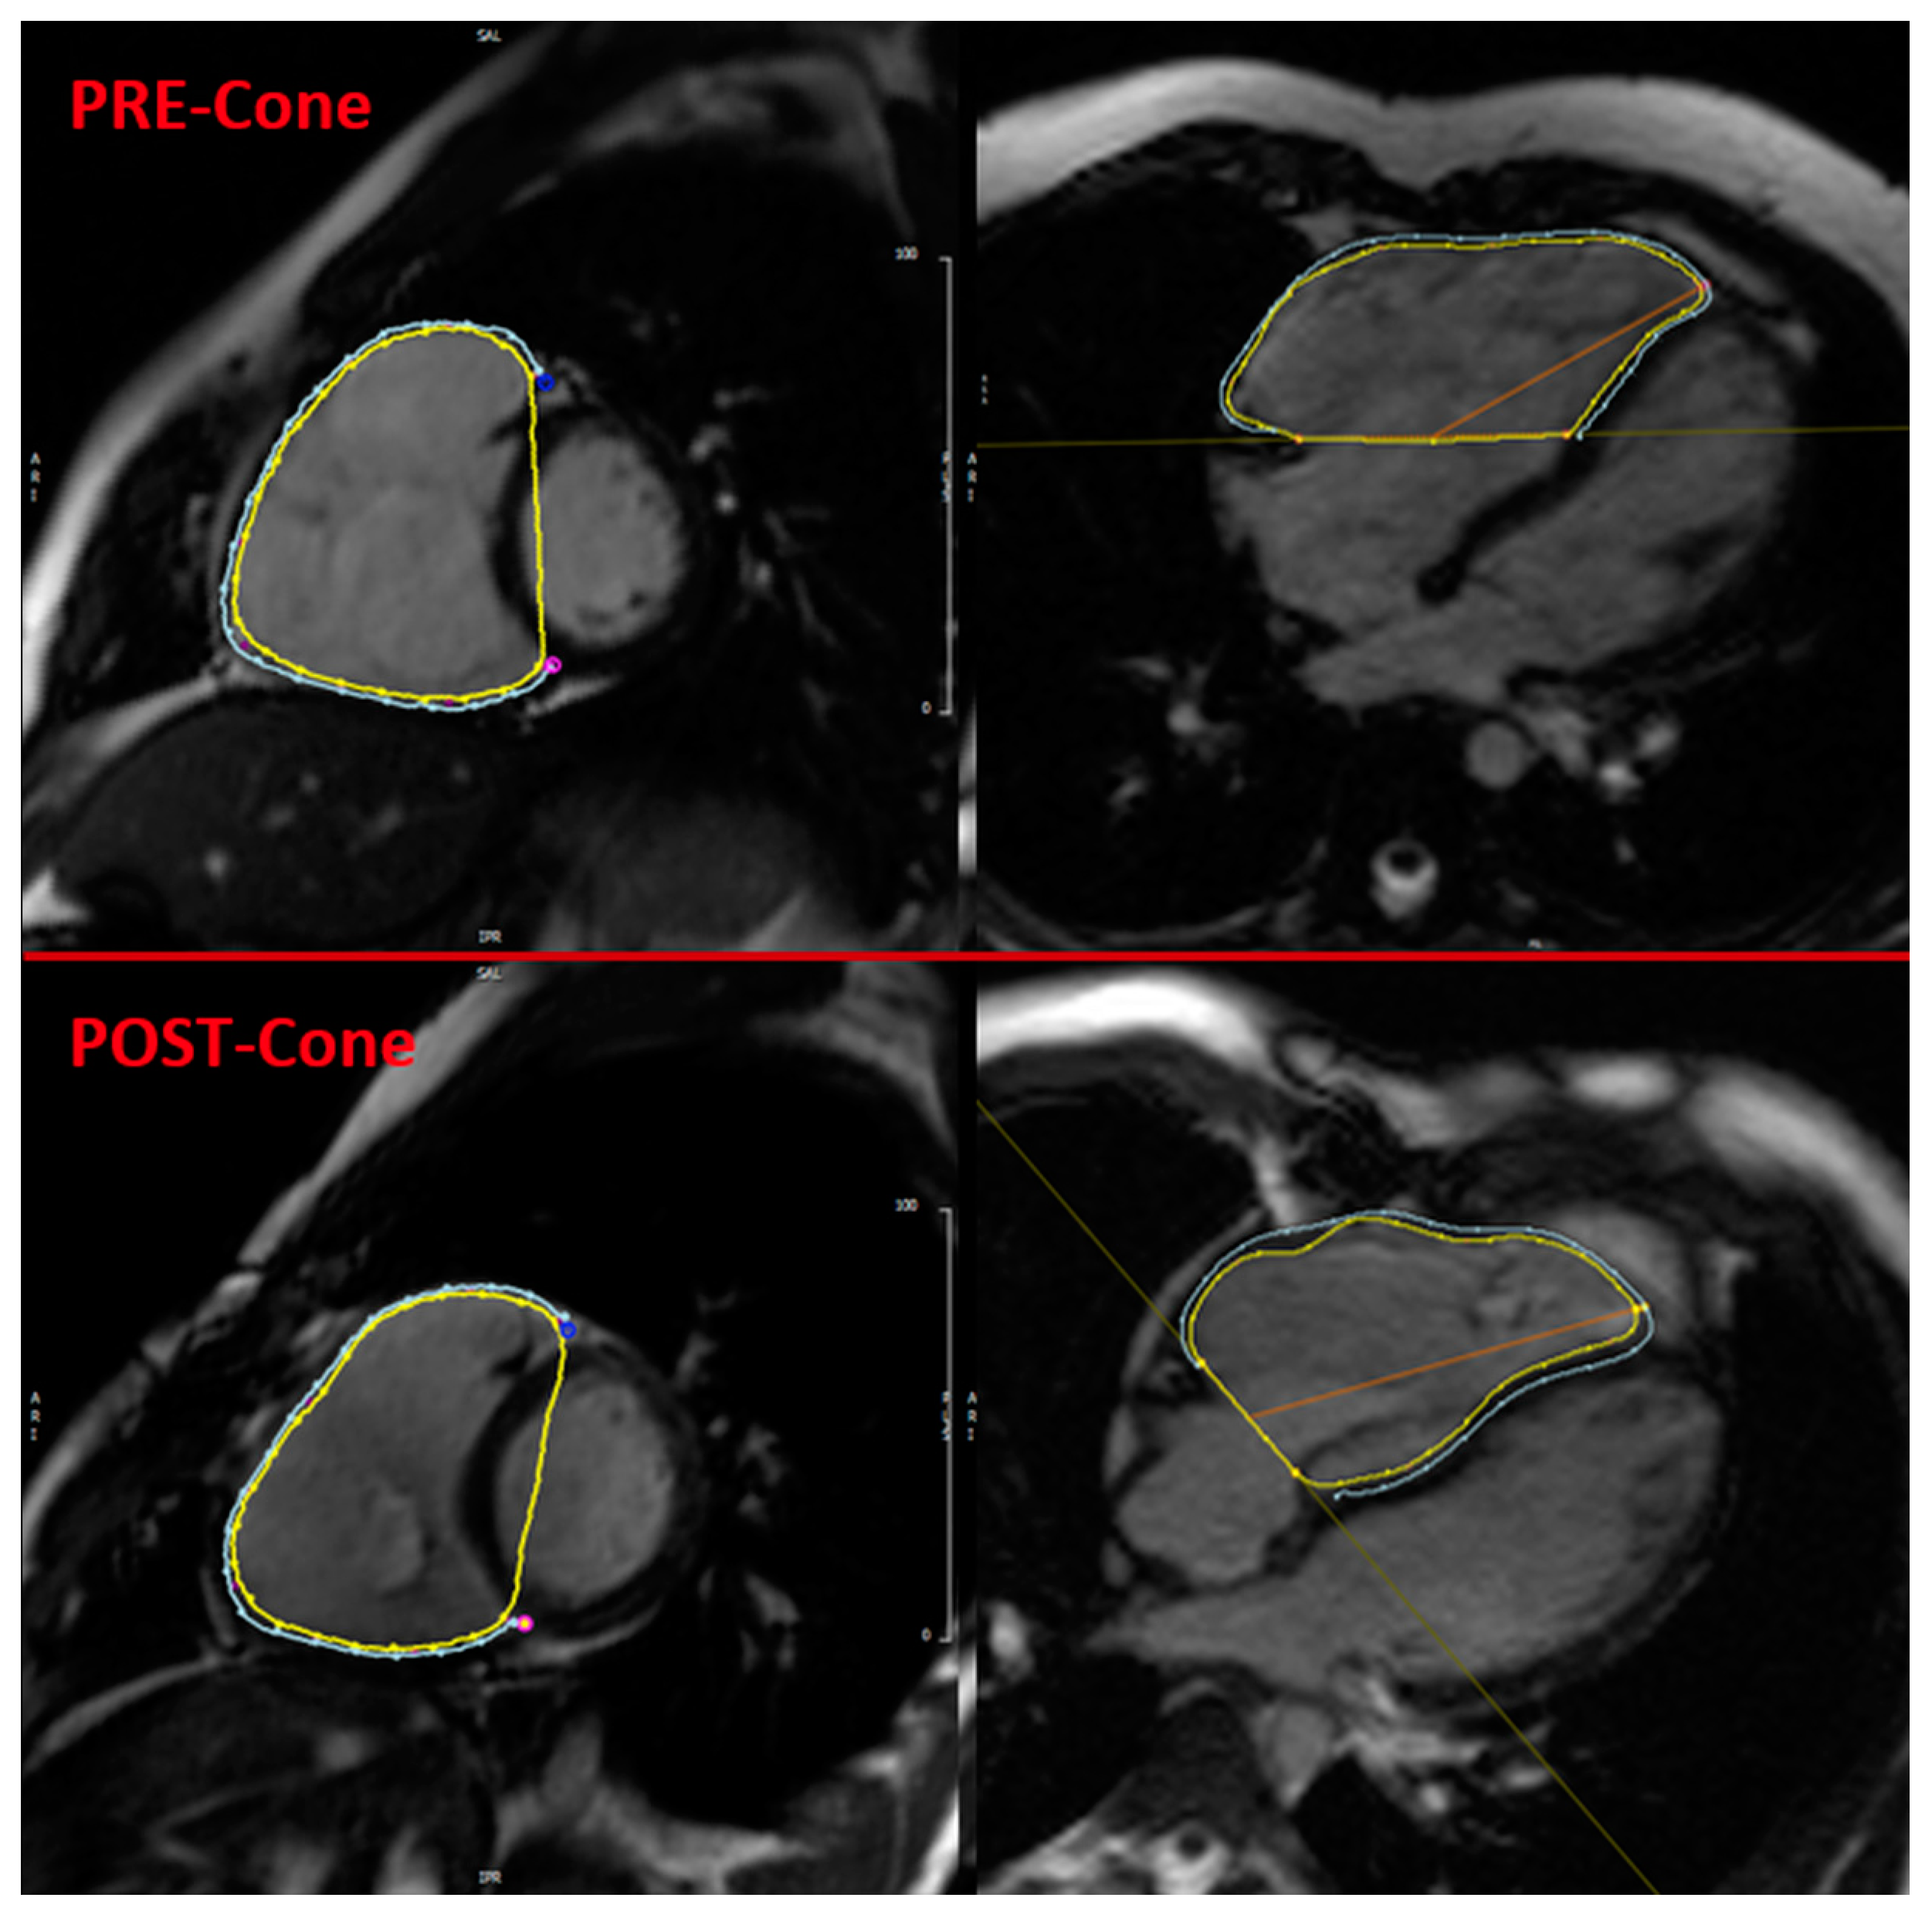

2.3. CMR Feature Tracking